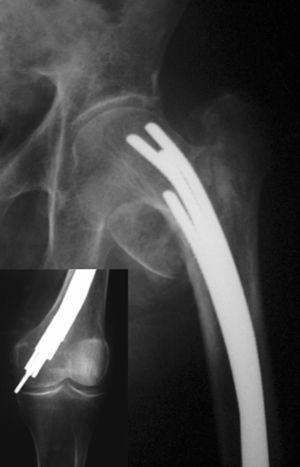

ComplicacionesSe produjo migración distal de los clavos en 104 pacientes (28%), siendo mayor de 2 cm en 67 casos (18%) (fig. 3). La correlación clínica entre migración, dolor y palpación de los clavos se observó en 41 casos (11%). La rotación externa de la pierna intervenida mayor de 10° se dio en 93 casos (25%). Dolor en rodilla en 86 pacientes (23%), de los cuales 28 no asociaban migración de los clavos mayor de 2 cm, ni palpación de los mismos. Migración proximal en 22 pacientes (6%) de los que 12 tenían dolor inguinal. Pérdida de corrección del ángulo cérvico-cefálico en 19 casos (5%). Acortamiento mayor de 1,5 cm en 37 pacientes (10%). Infección de la herida quirúrgica en 12 pacientes (3%). Parálisis del nervio ciático poplíteo externo en un caso. Rotura de los clavos en un caso. Pseudoartrosis un caso. Fractura supracondilea de fémur un caso.

Figura 3. Migración distal de clavos de Ender en una fractura pertro cantérea inestable, en un paciente con altas demandas funcionales.